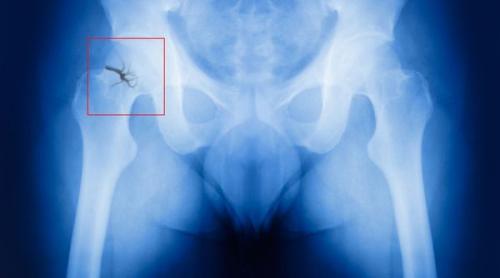

Одним из осложнений поздней постменопаузы является остеопороз. Он развивается из-за недостатка эстрогенов, который нарушает кальциевый обмен в организме. Кости становятся хрупкими, переломы возникают легко, буквально "на ровном месте".

Самый опас ный перелом в постменопаузе — перелом шейки бедра. Он никогда не срастается самостоятельно, т. е. без реконструктивных операций, и часто приводит к инвалидизации больных.

Перелом шейки бедра

Замечено, что развитию остеопороза особенно подвержены худощавые пациентки. Это связано с дефицитом жировой ткани, которая принимает участие в синтезе эстрогенов. Поэтому у женщин с умеренно развитой подкожно-жировой клетчаткой уровень эстрогенов выше.